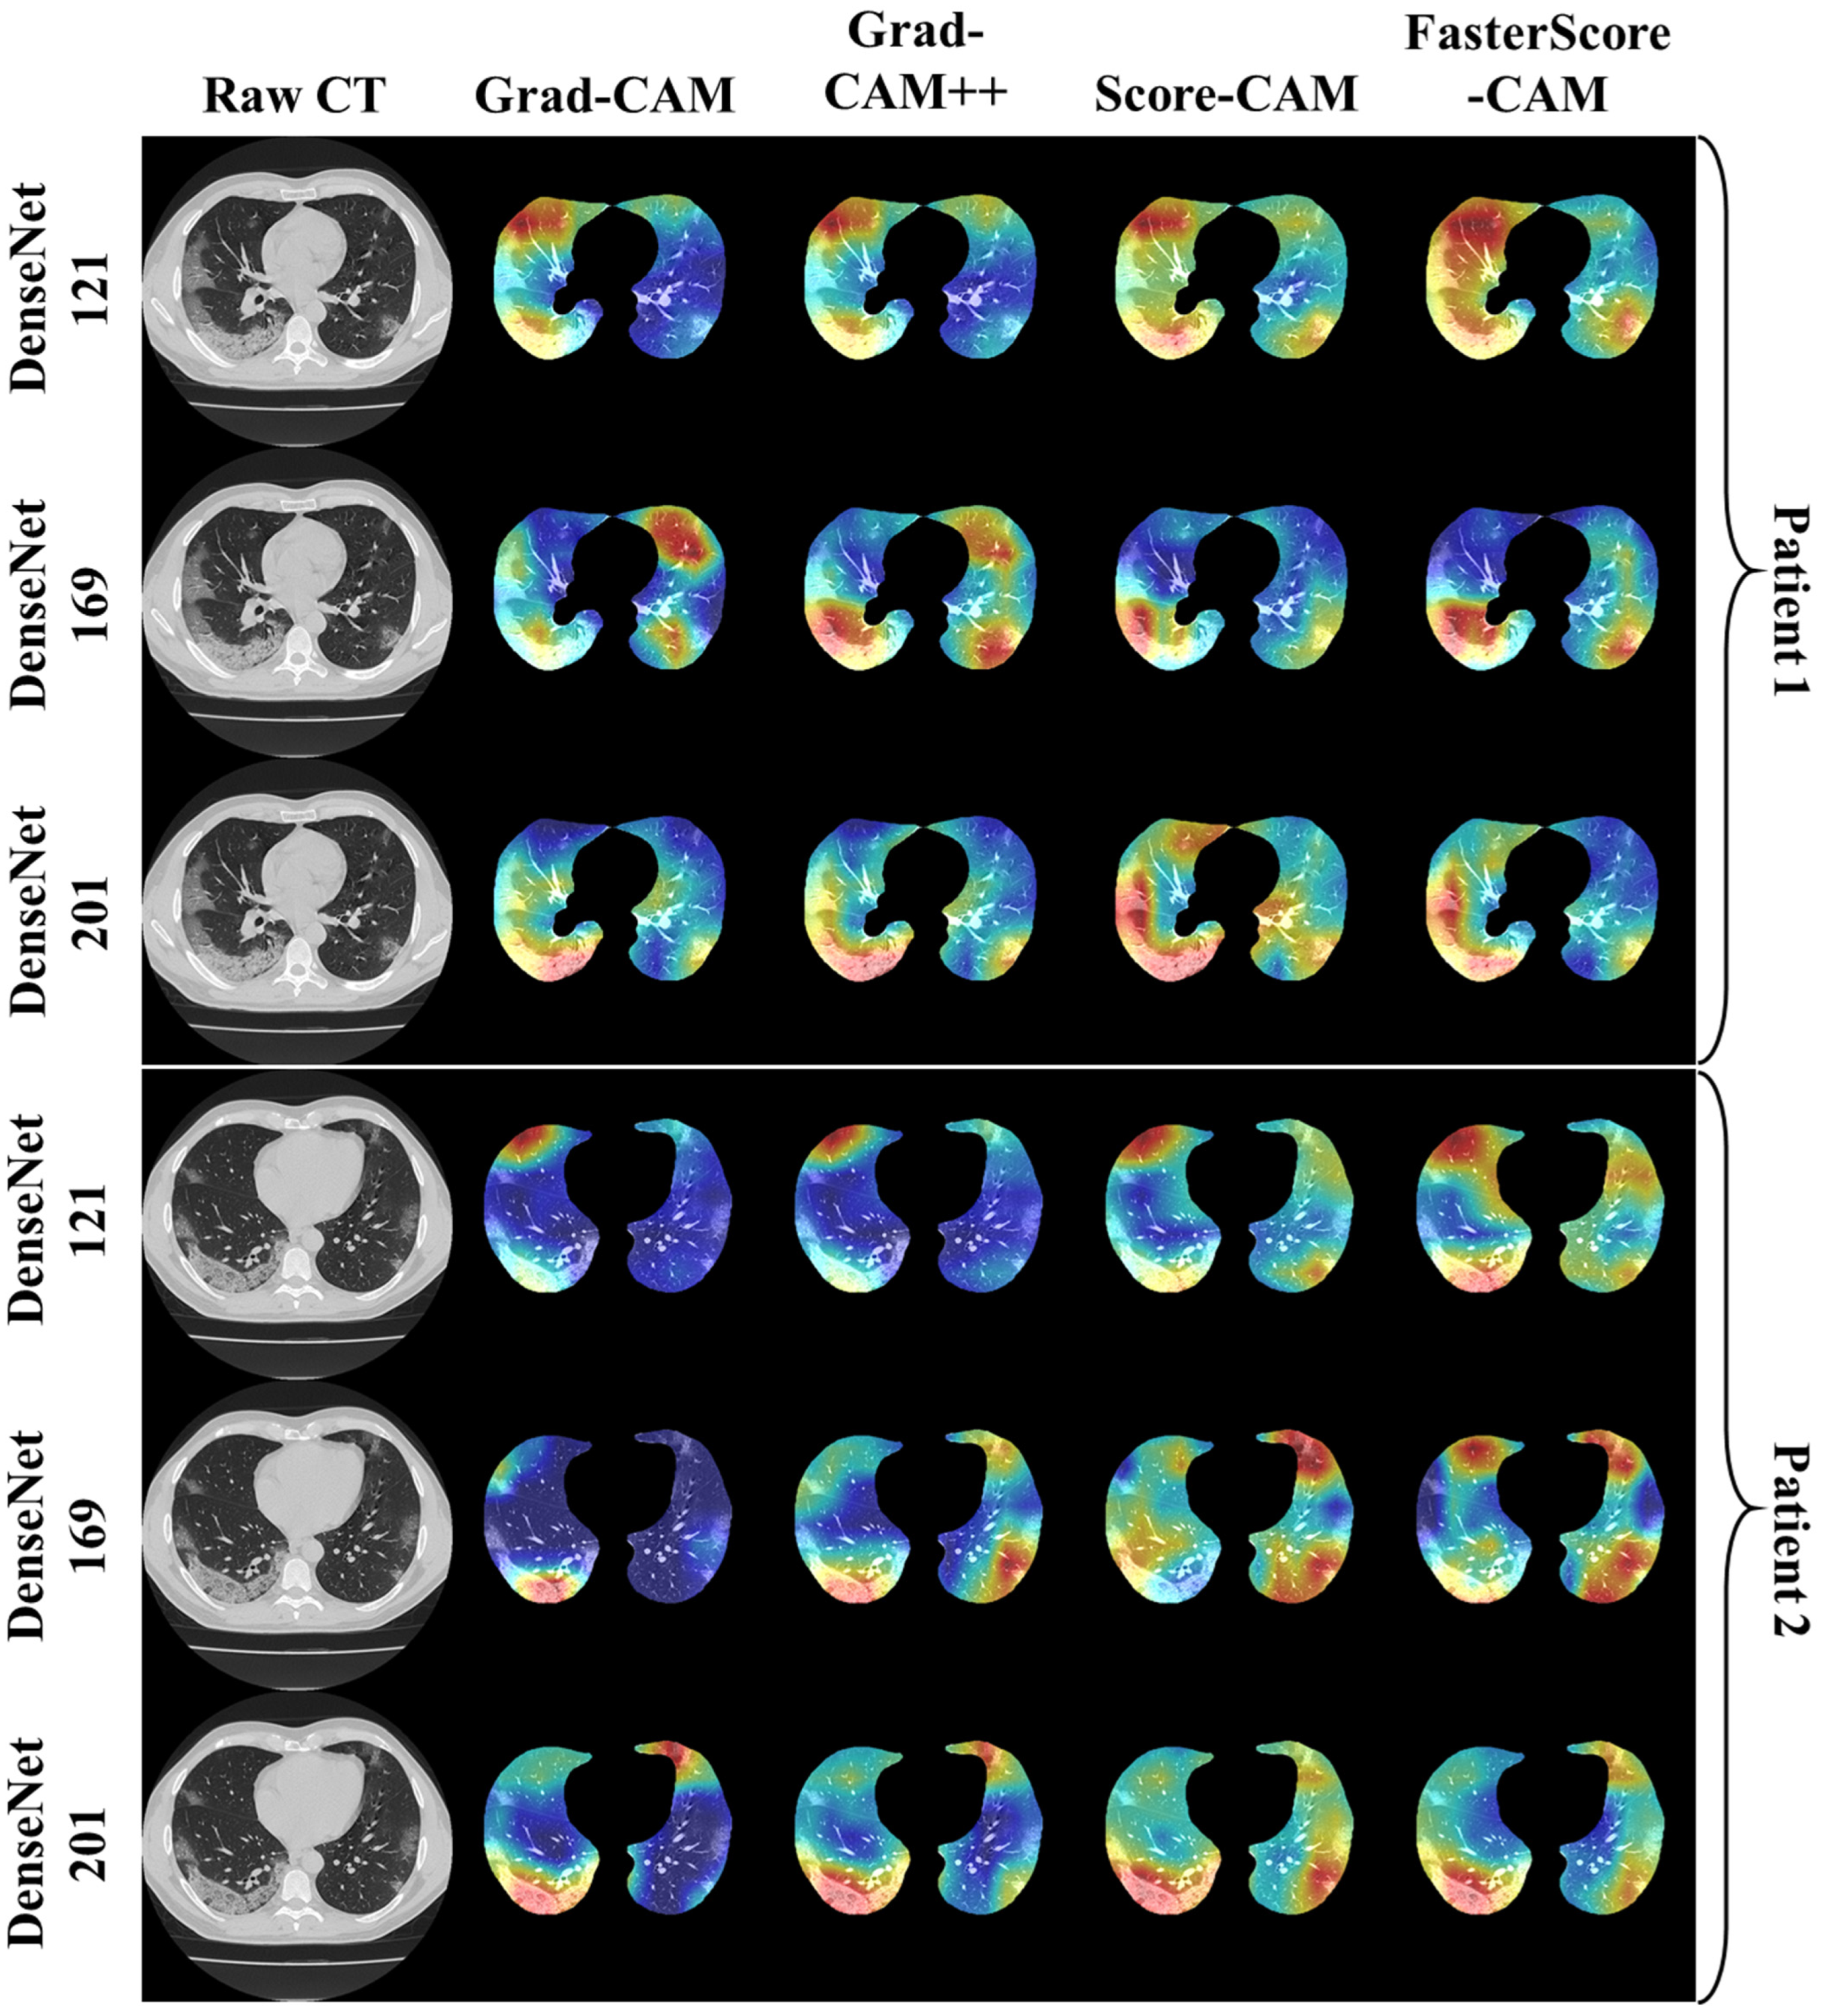

Visual Results Representing Lesion Using the Four CAM Techniques

4.1. Study Findings

4.4. A Special Note on Four CAM Models